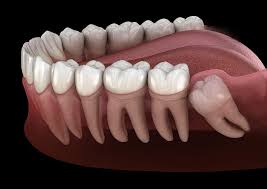

Răng khôn hay còn được gọi là răng cối lớn thứ ba, là răng cuối cùng phát triển và xuất hiện trong miệng. Chúng thường xuất hiện trong khoảng độ tuổi từ 17 đến 25, giai đoạn này trong cuộc đời được xem như giai đoạn bắt đầu sự trưởng thành hay thường được ví von là “độ tuổi khôn ngoan”.

THẾ NÀO LÀ RĂNG LỆCH. NGẦM?

Khi răng không mọc thẳng, đầy đủ trong miệng mà nằm nghiêng lệch hay ở bên trong xương hàm thì được gọi là răng bị lệch, ngầm (impacted tooth). Nói chung, răng lệch, ngầm thường là những răng không thể tách xuyên qua nướu được vì không có đủ chỗ mọc. Số người có răng lệch ngầm trong dân số là khá cao với tỉ lệ gần 90%.